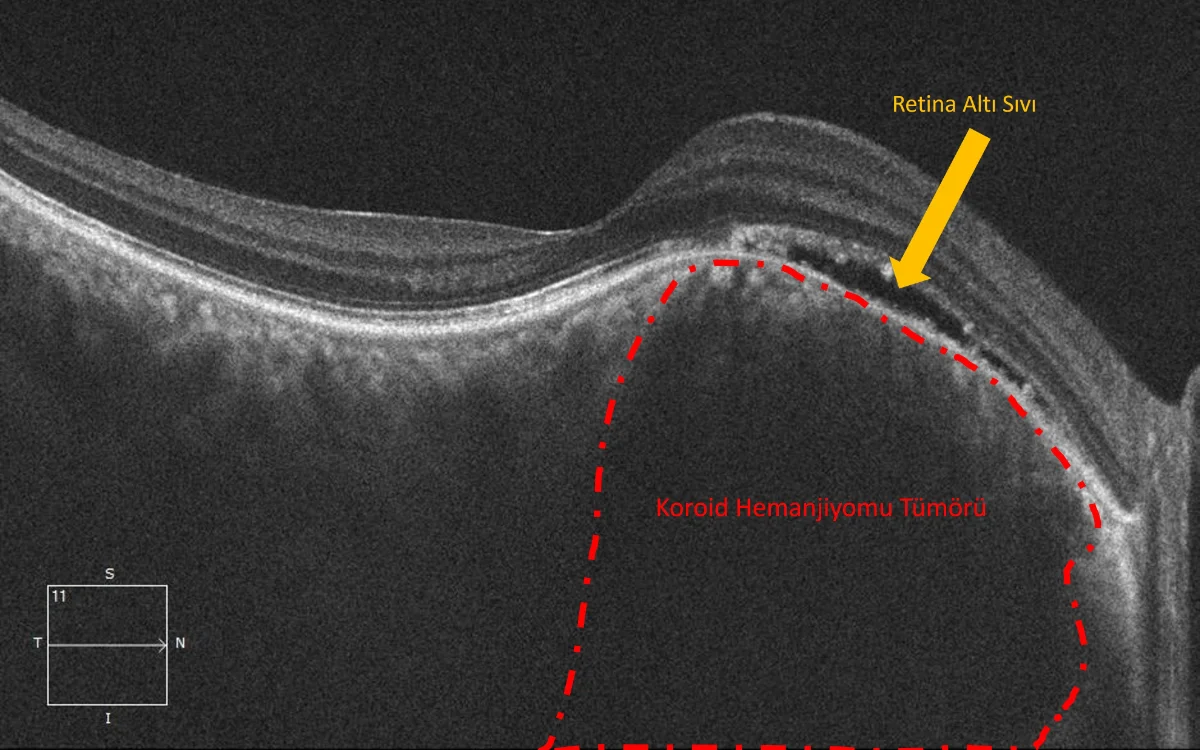

Koroid, görmeyi sağlayan sinir hücrelerinden oluşan retina dokusu ile gözün en dış tabakası arasında yer alır ve retinayı besleyen yoğun damar ağına sahiptir. Koroid hemanjiomunda bu damarlar anormal şekilde genişler ve süngerimsi bir damar kitlesi oluşturur. Bazı hastalarda bu damar yapısı retina altında sıvı birikmesine yol açarak görmede bulanıklık veya azalmaya neden olabilir.

Koroid hemanjiyomu tanısı konulması için öncelikle damlalı göz dibi muayenesi yapılması gerekir. Muayenede bu tümör retina altında, kabarıklık oluşturan kırmızı – turuncu nodüler bir yapı olarak gözükür. Daha sonra yapılacak olan OCT (optik koherens tomografi), floresein anjiyografi ve indosyinanin anjiyografi testleri ile tanı kesinleştirilir. Başka tümör veya kanserlerden ayrımının yapılması gereken atipik görünümdeki vakalara ultrasonografi ve MR incelemeleri de yapılabilir.